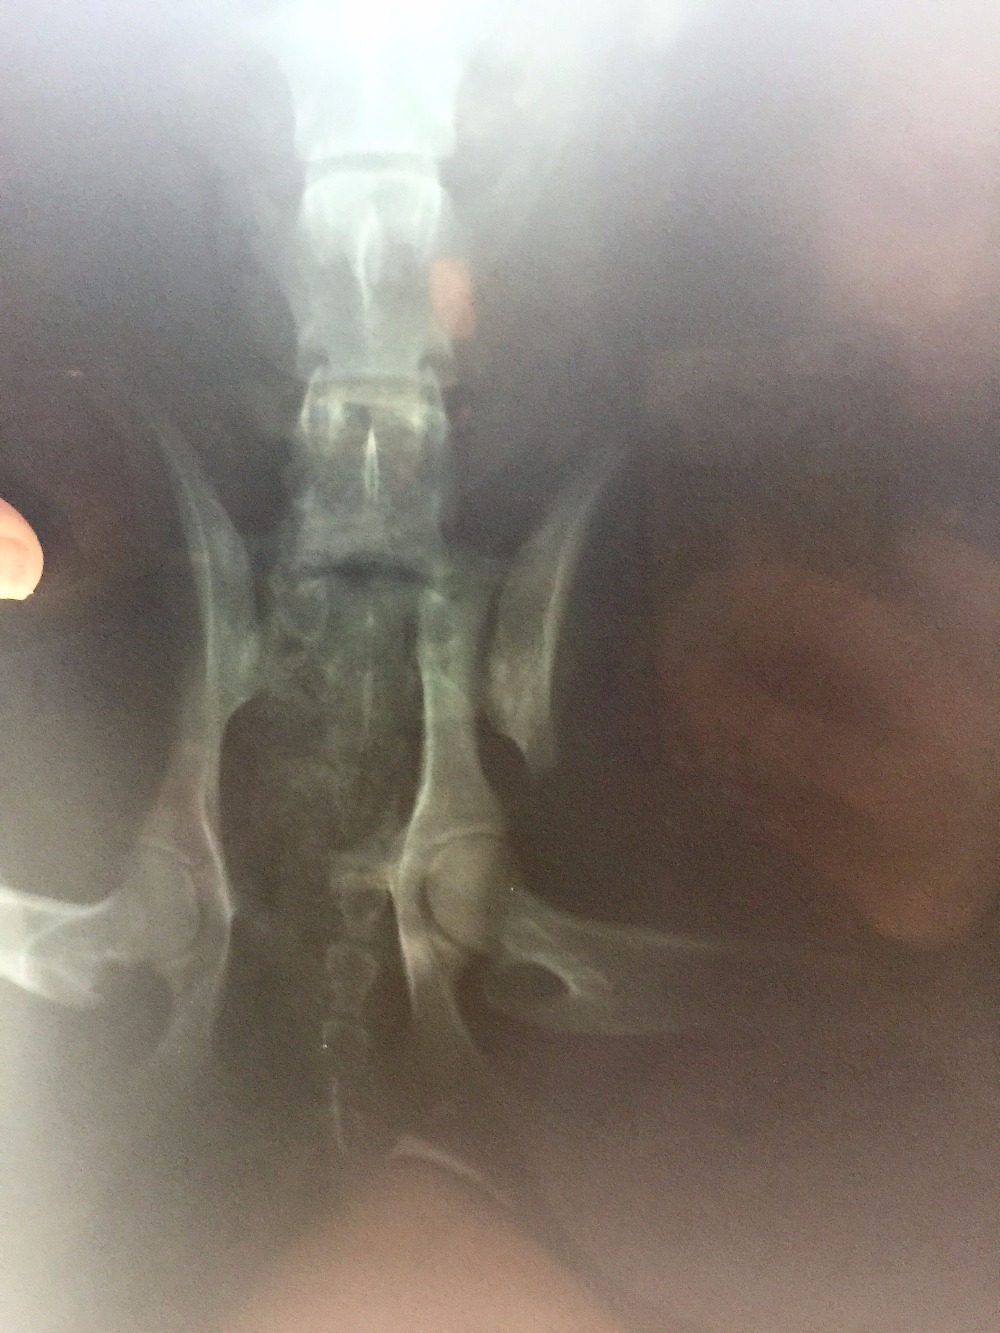

First, I want to thank everyone for their interest in helping this sweet girl. "Morgan" as she has been dubbed, was found on the side of the road (HWY 64 going into Morganton, NC) on 4/23/2016. It was super rainy and cold, and I was headed to Morganton to the feed store. We (my fiance and I) passed a dog sitting only 2-3 ft from the road in the pouring rain. I knew no dog would be sitting on the side of a super busy hwy in the wet and cold for no reason. We turned around and I jumped out of the car as quickly as possible, because we couldn't fully pull out of the road due to a ditch. I approached the dog and immediately realized my worse fears, that she had been hit. Without hesitation I immediately scooped her up, and this is where the story leads us. First off "Morgan" is extremely thin. No microchip, only a lime green collar with no tags. Looks to be (and comfirmed by vet) full-blooded Border Collie. Today she had X-rays and it was confirmed she has a fractured femur just above the knee on the right side, and another break to the bone that connects to the spine on the left side, and a fractured pelvis. She will require surgery and will be referred from the initial attending vet to someone for qualified to perform the surgery, because of the positioning of the femur break. She will require a plate in the femur. We are currently waiting on info from the Orthopedic Specialist of the initial vets choosing, and I will update as I get more info. Intitial vet believes surgery costs o be anywhere from $1200-$1800 (could be more). I WILL NOT give up on this girl, even if her owners have. If you are unable to help financially, prayers and good wishes are just as important and just as appreciated. Initial attending Vet is Dr. Pam Poteat at Forest City Animal Hospital in Forest City, NC. If you would like to confirm they do have a Facebook page with their phone number listed, but I will not list it here out of respect for them. The Orthopedic Surgery will be performed as soon as we can get a refferal and an appt. The Community Pet Center (a 501c3) organization will also be accepting donations on behalf of Morgan for those that would feel more comfortable donating to an organization rather than an individual. I would also like to speak on behalf of Morgan, she has been nothing but an angel and extremely trusting of me from the very beginning of our journey together, and she deserves to live out a long, healthy happy life. She is still very young and has so much left to see and do. Thankyou so much from the bottom of my heart.